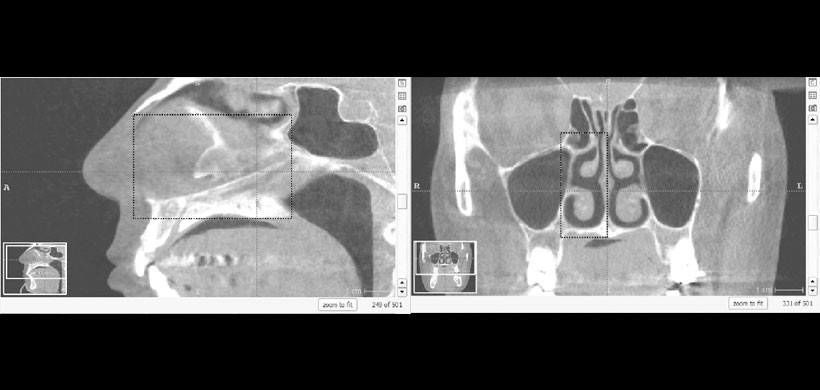

Fig 1. CBCT, en el cual se muestra la selección del área de interés a determinar el volumen del espacio aéreo de las fosa nasal derecho, se aprecia que existen parámetros a tener en cuenta, la línea media sagital, el paladar duro, el área tiene que ser visualizado de manera sagital y de manera frontal para poder tener la cobertura total.

Fig 2. CBCT, determinación de los volúmenes del espacio aéreo de las fosas nasales, posteriormente se realiza una diferencia de lados y se determina la discrepancia para ver el grado de severidad de la desviación del tabique nasal.